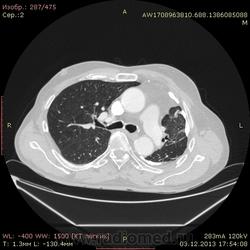

Ребята, вы что, какая жидкость? Чистая известь, посмотрите в костном окне. Отставить натив (в данном случае, хотя для аневризм он обычно нужен). Отставить тромбоз верхней полой вены (потоковые артефакты, не дело вены в артериальную фазу оценивать). Отставить аневризму  аорты, поперчник восходящего отдела на уровне легочного ствола 42мм. А вот легочная гипертензия, здравствуй: поперечник легочного ствола - 37мм, ПЛА - 25мм, ЛЛА - 25мм, НАо - 25-34мм.

Для справки: холестериновые камни имеют плотность менее 100 ед.Н. Имеющаяся хренотень в левом гемитораксе имеет плотность больше костной, до 1500 ед.Н. Вопрос: какая химико-физико-биологическая реакция может способствовать превращению мягинькаво холестерина в термоядерную плевральную лепёшку?)